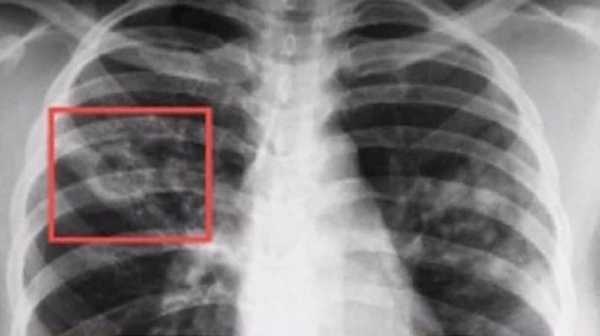

В подавляющем большинстве случаев человеческий организм инфицируется палочкой Коха, и в первую очередь местом локации патогена является легочная ткань. При этом начало патогенеза протекает латентно, и человек не догадывается о наличии заболевания, поэтому в большинстве случаев туберкулез диагностируется после рентгенологического обследования (подробней читайте тут), когда на фото флюорографии видны характерные затемнения. Более подробно об этом рассказывается на видео в этой статье.

Флюорография – обязательное скрининговое обследование, помогающее выявить ранние формы болезни